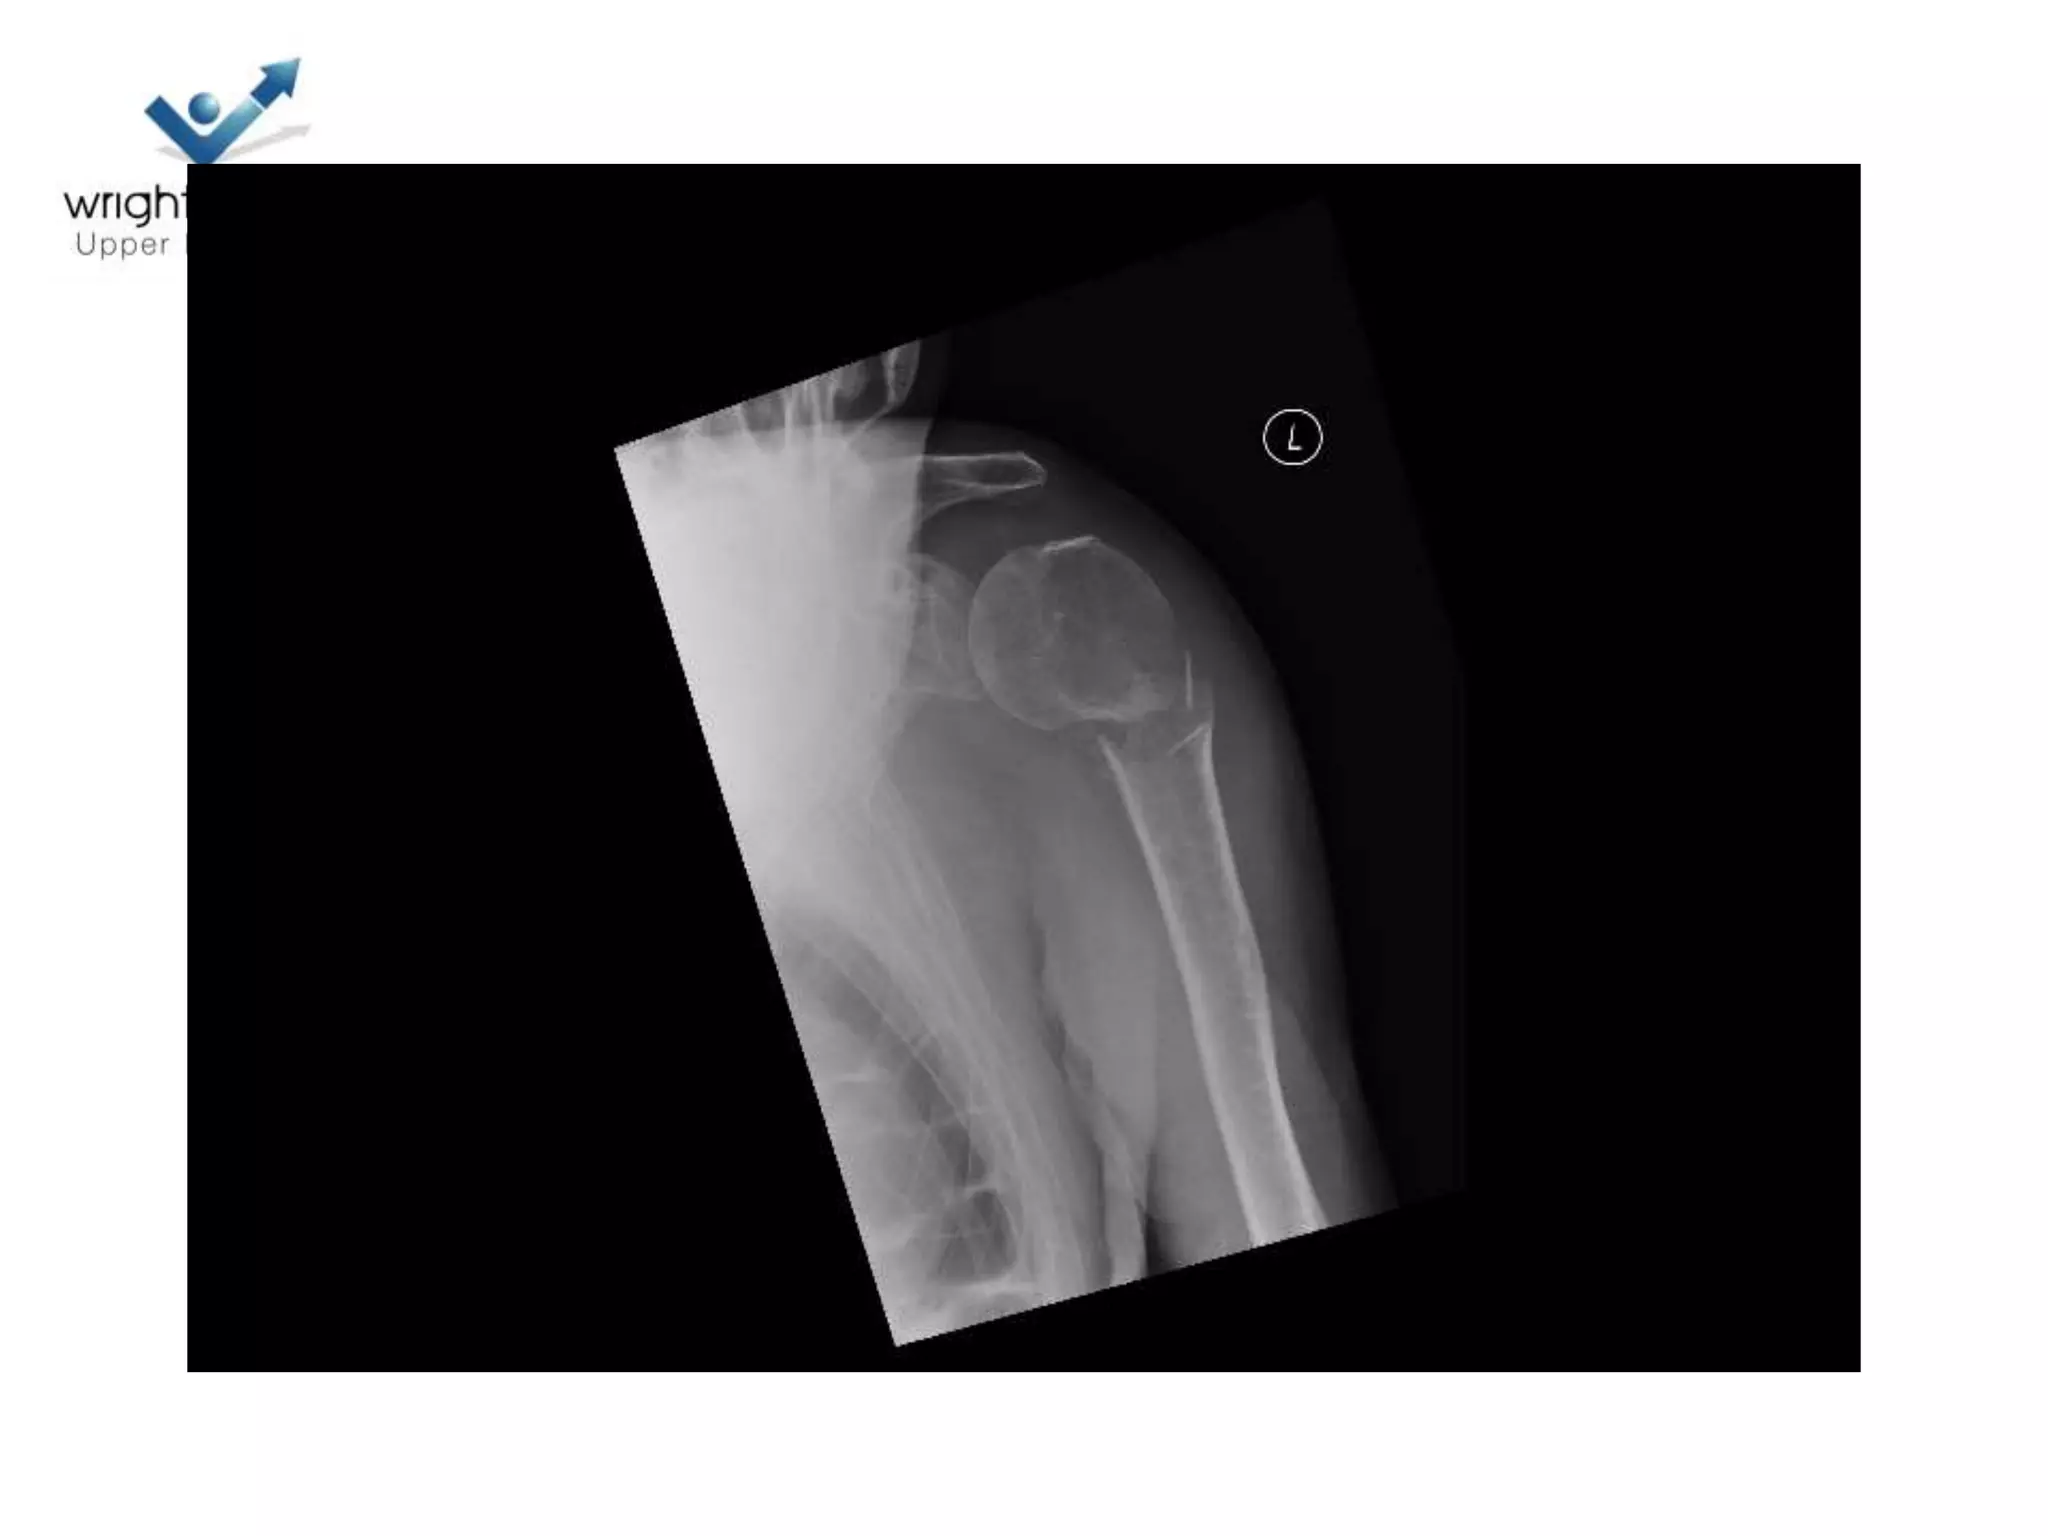

Head Ischaemia

1. Posteromedial Calcar

Predictor no 2.Medial Hinge

Medial Hinge